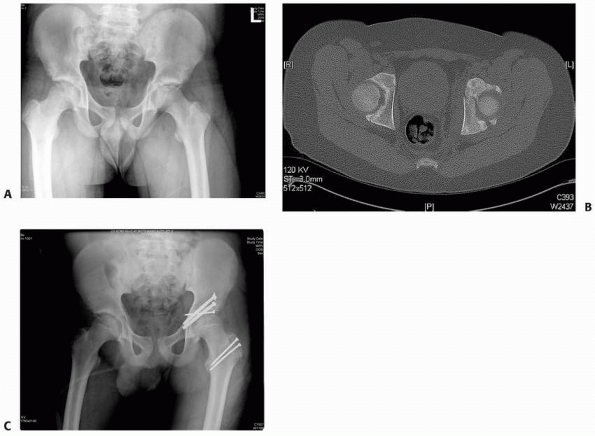

FIGURE 20-18 A.

Multiple trauma in this 12-year-old child included three fractures of the pubic rami, disruption and fracture of the sacroiliac joint on the right, and a femoral shaft fracture on the right. B. CT shows fracture of the ilium and disruption of the sacroiliac joint. C. After open reduction and internal fixation of the sacroiliac joint and closed intramedullary nailing of the femoral shaft fracture. Note femoral nail inserted through the tip of the greater trochanter. |